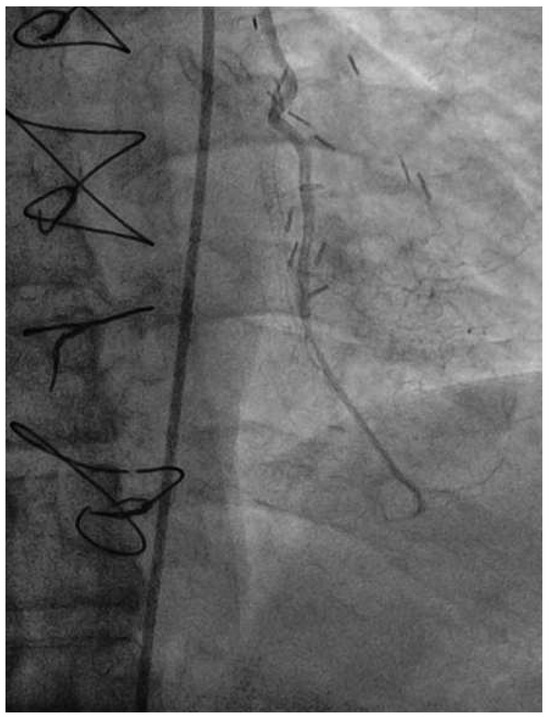

Veno-arterial extracorporeal membrane oxygenation (ECMO) is utilised as a short-term mechanical circulatory assist device for treatment of refractory acute cardiogenic shock. After a period of support, called “bridge to decision”, the options for ens...